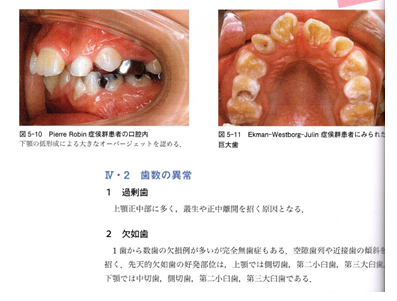

次に矯正学では歯の欠如は異常とみている事を確認していきましょう。

抜歯矯正の好きな先生は簡単にノンカリエスの上下の第一小臼歯を4本抜いてしまいますが歯が4本足りない歯列の咬合は明らかに異常咬合です。

抜歯矯正の先生は欠如の場合は隙間が出来ますが、矯正はその後に隙間を埋めて綺麗に並べるから良いのだと考えられていますが、ホントにそうでしょうか?